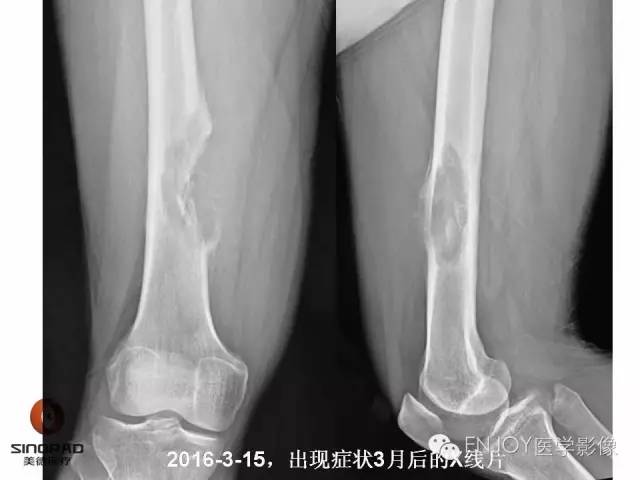

【病例】右侧股骨多形性肉瘤1例X线及MR影像表现

多形性肉瘤(以往称为:恶性纤维组织细胞瘤)